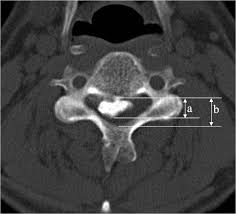

Axial Canal Occupying Ratio:

•   Obtain a CT scan of the cervical spine with axial images through the OPLL

•   Identify the axial CT slice at the level of the maximum OPLL thickness (diameter “D”) (the most prominent point of the ossification)

•   Measure the anteroposterior (AP) diameter of the spinal canal at the level of the maximum OPLL, from the posterior vertebral body cortex to the inner cortex of the lamina

•   Measure the maximum thickness of the OPLL (diameter “d”) at the same level, from the posterior vertebral body cortex to the most posterior extent of the ossification

•   Calculate the COR: COR (%) = (d / D) × 100